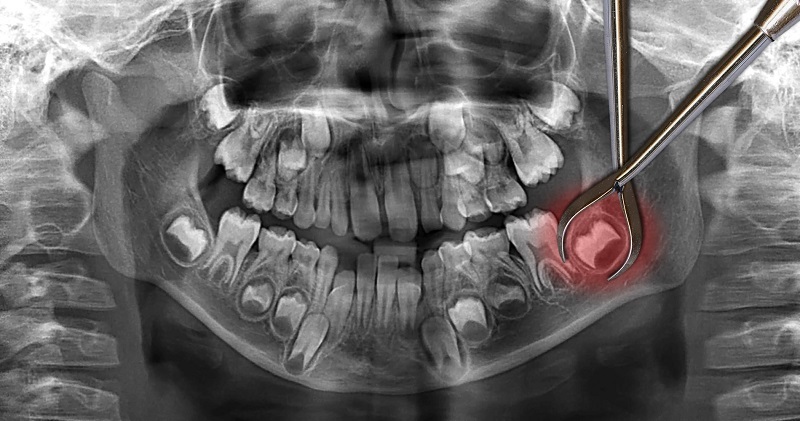

Всё начинается с осмотра и рентгена. Врач должен знать, как располагается моляр и какая у него корневая система. От полученных данных зависит тактика удаления.

Сложная экстракция

Если восьмёрка дистопирована, ретинирована или всё сразу, то быстро и просто избавиться от неё не получится. Для удаления проблемной восьмёрки врач может использовать скальпель, бормашину, лазер, элеватор и другие хирургические инструменты. Этапы операции:

- Местная или общая анестезия.

- Антисептическая обработка.

- Рассечение десны, разведение её краёв и обнажение зуба.

- При необходимости высверливание или отсечение костной ткани, разделение зубного корня на несколько частей.

- Полное или частичное извлечение зубной единицы.

- Остановка кровотечения.

- Обработка ранки антибактериальными и противовоспалительными медикаментами.

- Сшивание мягких тканей.

Длительность сложной экстракции — от 30 минут до 2 часов. Если для сшивания десны применялись нерассасывающиеся нити, через 7-10 дней необходимо обратиться в клинику для их снятия.

| Удалить зуб мудрости с верхней челюсти легче, чем с нижней. Всё потому, что корень у верхних моляров ровный и небольшой, а у нижних — сложный и запутанный. Плюс ко всему нижняя челюсть плотнее и массивнее верхней. |